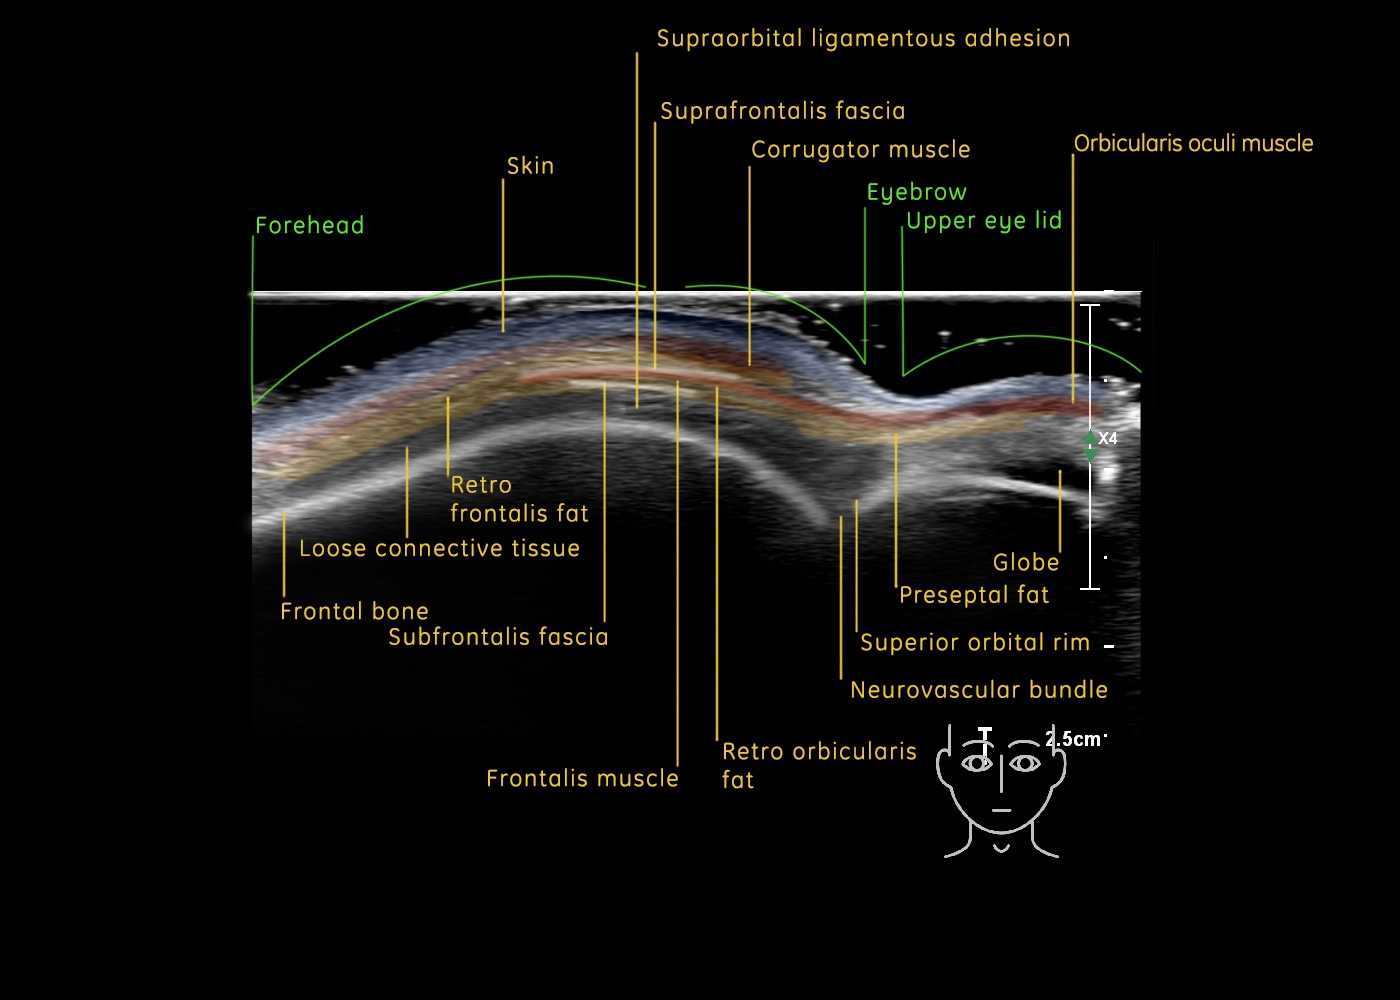

In this section you will learn more about the different layers of the face with the use of ultrasound. When you click on the secondary ultrasound image, you will see the different structures as an overlay. This will help to train yourself to recognize the different layers of the face.

Study the first image to recognize the different layers. If you are sure about the layers, swipe to the second image to view the answer (if applicable).